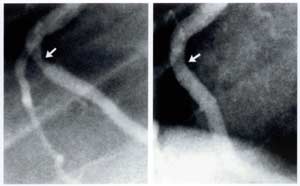

Below are angiograms, imaging of arteries, showing atherosclerosis, arterial blockages, that were reversed by being on plant based diets. The restriction of fat intake was key to reducing the plaque build up.

Coronary angiograms of right coronary artery before (left) and showing 30% improvement (right) following approximately 60 months of a plant-based diet and cholesterol-lowering medication.

Caldwell B. Esselstyn, Jr., MD

Cleveland Clinic Foundation